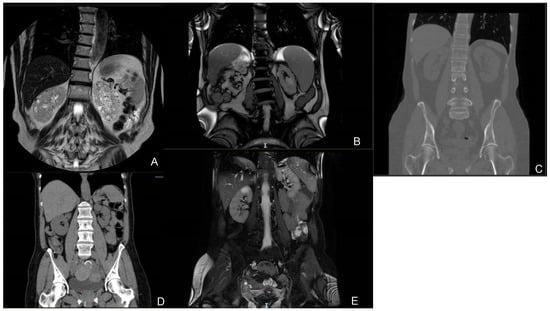

| Patient 1 (67) | NM_016306.5:c.716T>G p.(Leu239Ter) 4 / | Regular-sized kidneys (10/10) Bilateral cortical millimetric cysts | No cysts | Yes (67) | Creat. 1.58 mg/dL eGFR 46 mL/min/1.73 m2 CKD IIIa | Creat. 2.50 mg/dL eGFR 26 mL/min/1.73 m2 CKD IV | −4 | MGUS, mild bilateral perceptive hearing loss, hyperuricemia |

| Patient 2 (67) | NM_016306.5:c.134A>G p.(Tyr45Cys) 4 gnomAD Exomes: Version: 2.1.1ƒ = 0.00000797; gnomAD GenomesVersion: 2.1.1ƒ = 0.0000319 | Regular-sized kidneys (11/13) Bilateral millimetric cysts and some bigger cysts | No cysts | Yes | Creat. 2.45 mg/dL eGFR 27 mL/min/1.73 m2 CKD IV | Creat. 4.16 mg/dL eGFR 14 mL/min/1.73 m2 CKD V | −4.3 | Nephrolithiasis, AMI, AF, severe mitral insufficiency |

| Patient 3 (61) | NM_016306.5:c.456+3_456+6del (IVS4) 4 / | Regular-sized kidneys (10.9/10.5) Bilateral millimetric cysts | No cysts | Yes (55) | Creat. 1.04 mg/dL eGFR 59 mL/min/1.73 m2 CKD IIIa | Creat. 1.14 mg/dL eGFR 52 mL/min/1.73 m2 CKD IIIa | −2.3 | Microhaematuria, recurrent cystitis, nephrolithiasis, mild tricuspid insufficiency, mild neurosensorial hearing loss in the left ear |

| Patient 4 (59) | NM_016306.5:c.456+3_456+6del (IVS4) 4 / | Regular-sized kidneys (10.3/9.4) Bilateral millimetric cysts | Multiple cysts | Yes (50) | Creat. 1.27 mg/dL eGFR 46 mL/min/1.73 m2 CKD IIIa | Creat. 1.27 mg/dL eGFR 46 mL/min/1.73 m2 CKD IIIa | N/A | / |

| Patient 5 (46) | NM_016306.5:c.499C>T p.(Arg167Trp) 3 gnomAD ExomesVersion: 2.1.1ƒ = 0.00000398; gnomAD GenomesVersion: 2.1.1 / | Regular-sized kidneys (10/10) Bilateral millimetric cysts | One cyst in the III segment (4 mm) | No | Creat. 1.54 mg/dL eGFR 40 mL/min/1.73 m2 CKD IIIa | Creat. 1.54 mg/dL eGFR 40 mL/min/1.73 m2 CKD IIIa | N/A | Hyperuricemia, reactive anxiety depressive syndrome |